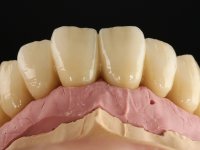

Realizada uma TAC, foi planificada a colocação de 6 implantes no maxilar superior. Foi decidida a colocação de dois implantes na zona dos incisivos centrais, dois implantes na zona dos caninos e dois na zona dos segundos pré-molares. A ausência de estrutura óssea na zona distal do primeiro quadrante implicava a realização de uma regeneração óssea no seio maxilar direito. A cirurgia foi realizada e após a colocação dos implantes foi feita a impressão para confeção de uma prótese provisória metalo-acrílica aparafusada para colocação em carga imediata no dia seguinte. O implante colocado na zona do seio maxilar direito não foi colocado em carga. Passados 6 meses foi realizada a impressão aos 6 implantes com técnica de moldeira aberta e foram confecionados os modelos de trabalho. Numa consulta seguinte foram montados os modelos de trabalho em articulador semi-ajustável utilizando o arco facial e a relação inter-maxilar obtida com a prótese provisória. Foi feita uma muralha de silicone sobre a ponte provisória com o objetivo de orientar o trabalho laboratorial. Realizada a infra estrutura metálica aparafusada esta foi provada em boca e finalmente após colocação de cerâmica o trabalho foi colocado definitivamente. Como passaram vários meses após a realização da primeira TAC foi feita uma segunda para planificar a colocação de implantes no 4º quadrante. Colocaram-se 3 implantes na mesma sessão em que foi feita a extração dos pilares da ponte. Estes implantes foram posteriormente reabilitados com uma ponte metalo-cerâmica aparafusada de três elementos.